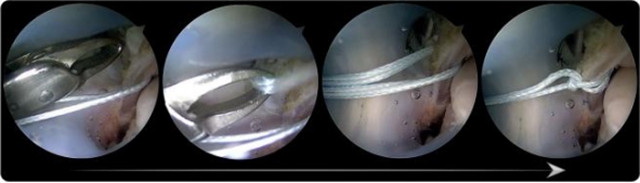

开展关节镜下应用ATiFL的远端束转位加强修复治疗踝关节外侧不稳的修复手术和早期康复诊疗方案。

张磊说:“这个技术定位病灶准确,切实解决了临床难点。之前1个小时才能完成的手术,现在打两个5mm的小孔,15-20分钟就完成了。”为超重、运动要求高的患者或质量欠佳的ATFL损伤提供一种新的治疗技术。